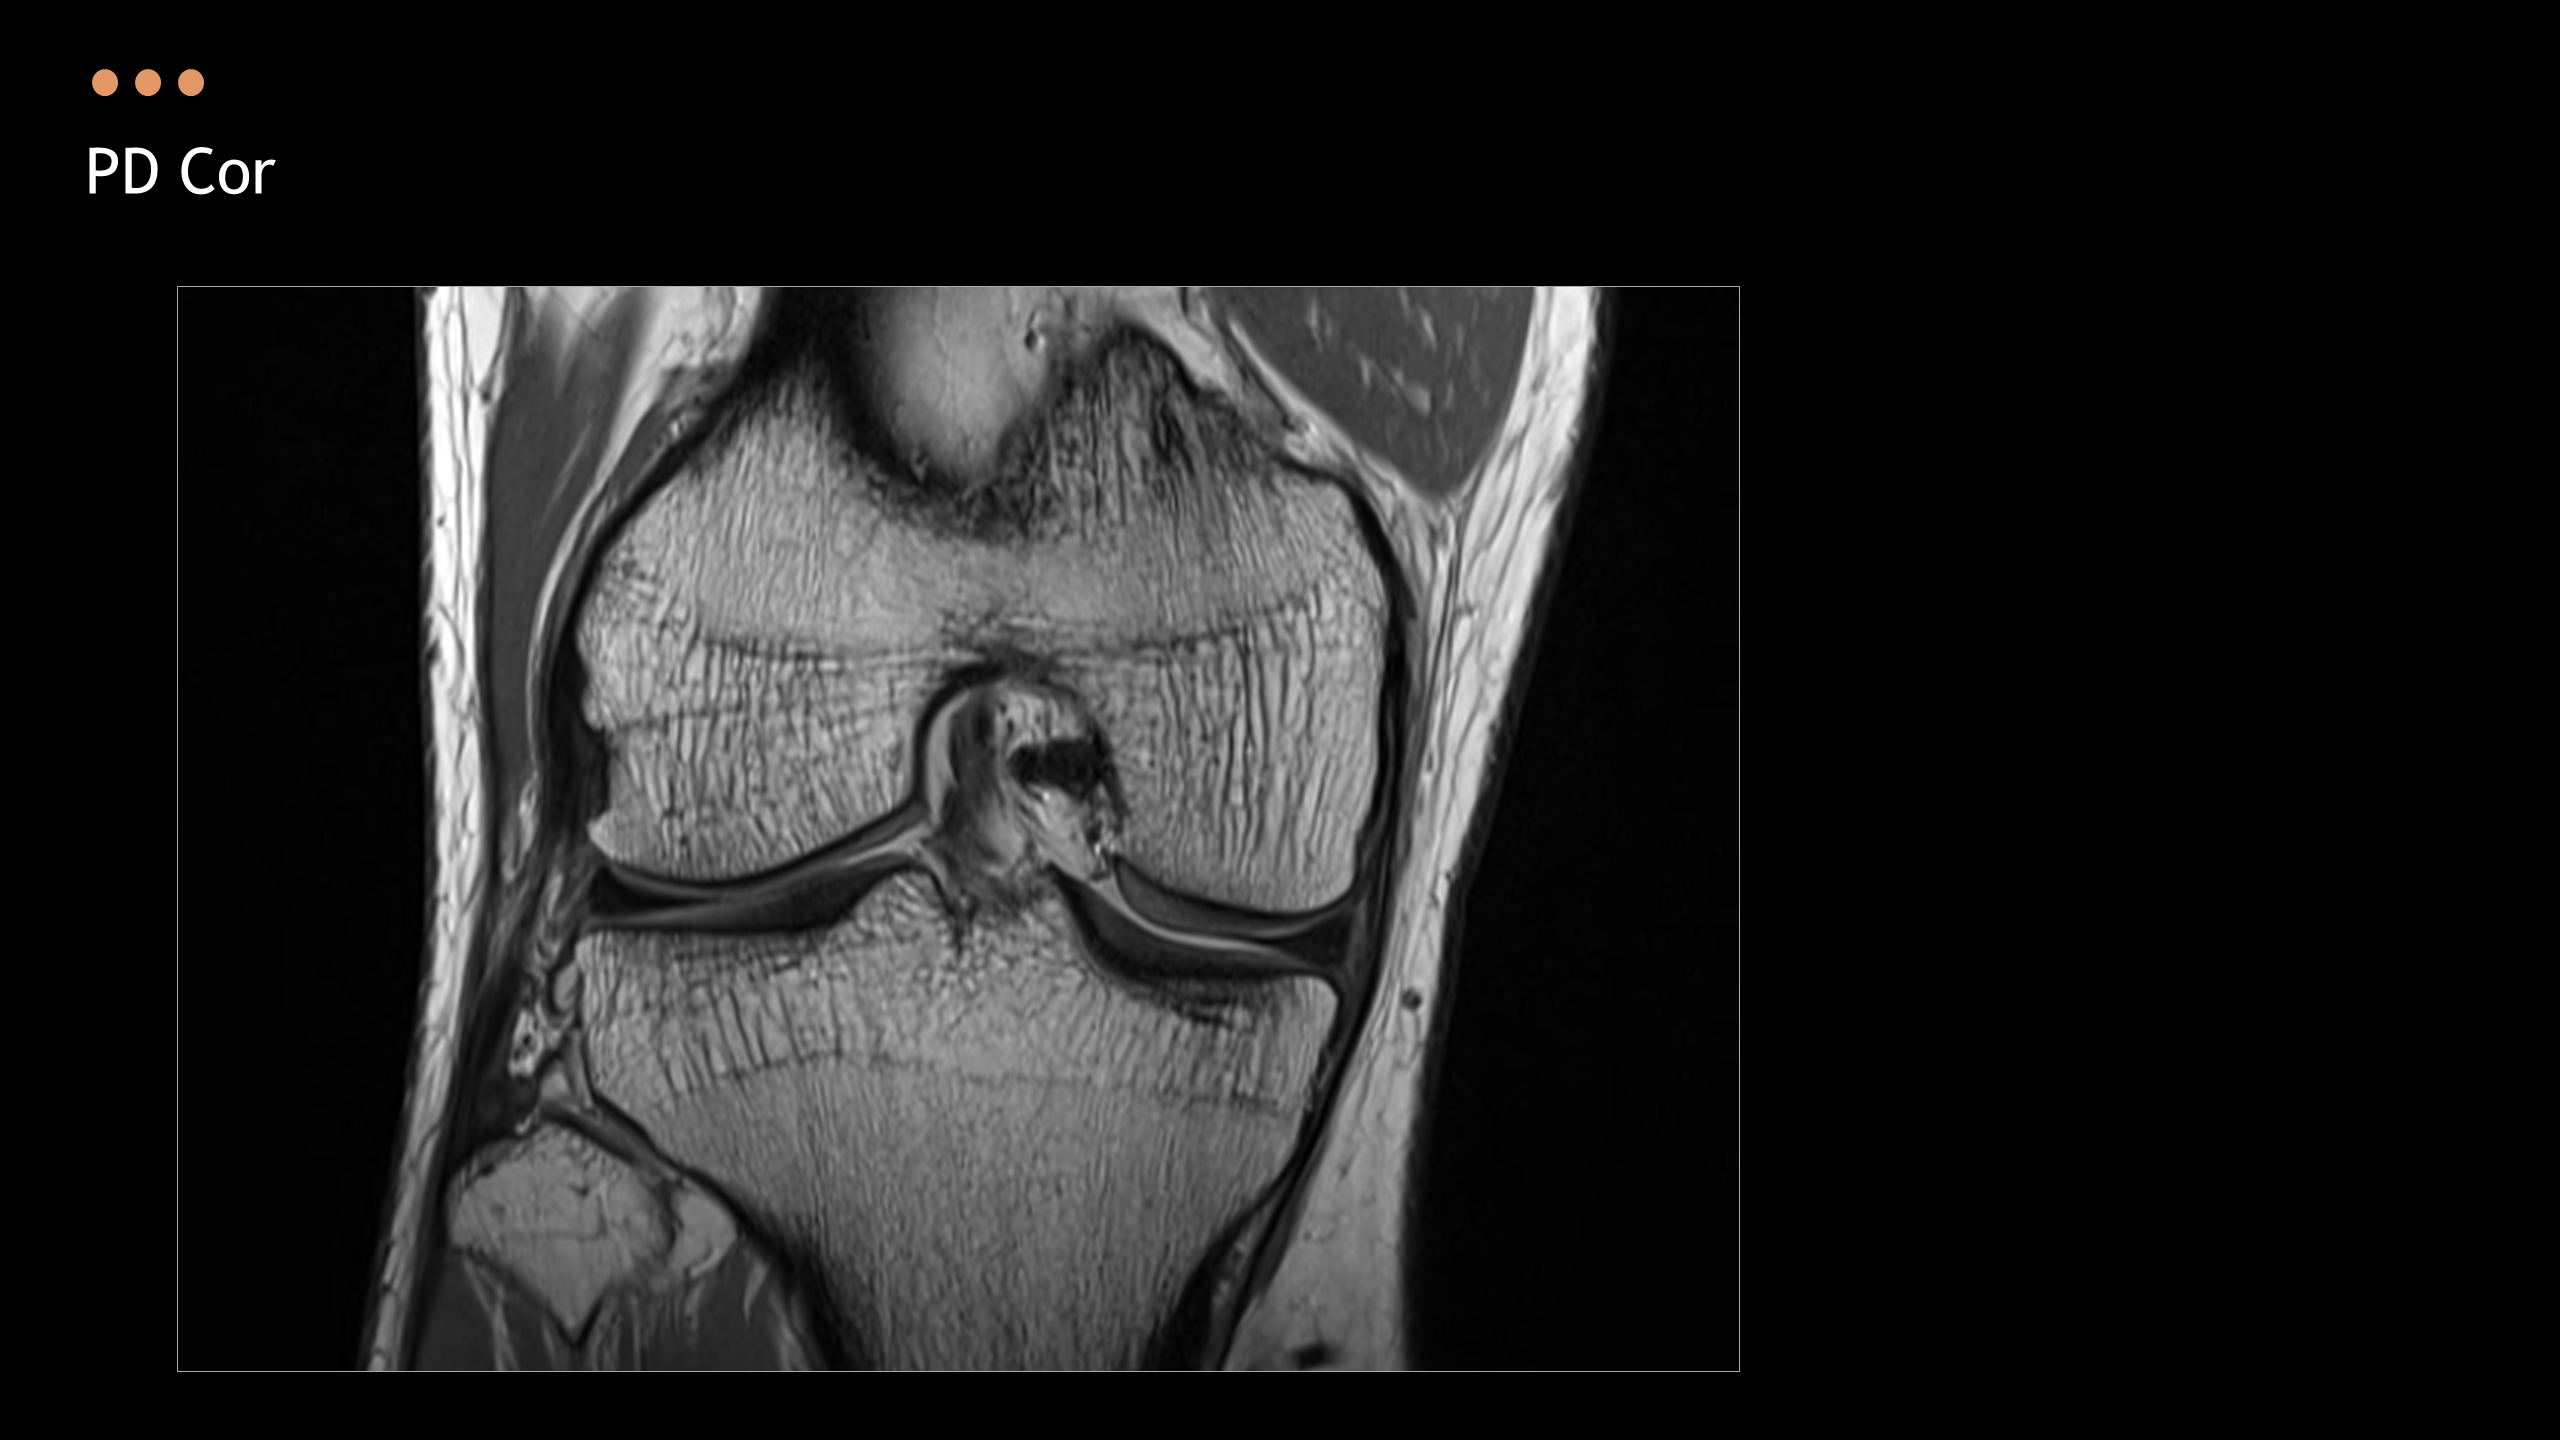

아래의 Normal Knee MR Anatomy를 숙지하고 오셔야, 강의에 어려움이 없습니다.

Detailed Knee MRI Anatomy [대한연부조직한의학회].pdf